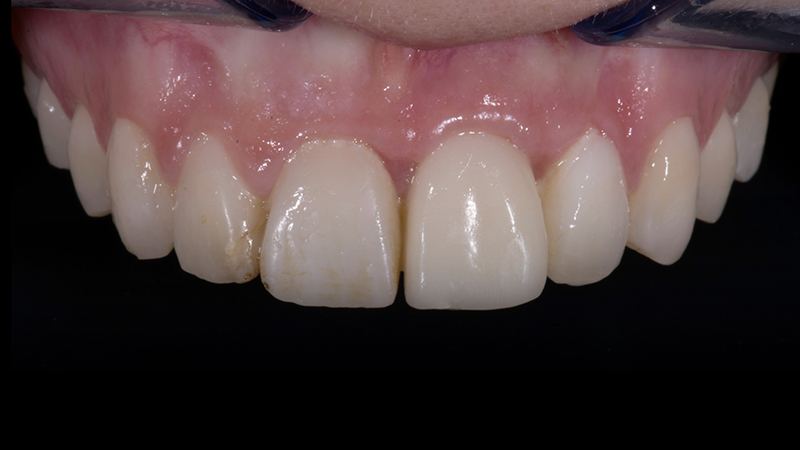

Innovazioni tecnologiche e materiali sempre più performanti mi hanno permesso di ridurre i tempi di terapia e il disagio per i miei pazienti e di aumentarne il margine di profitto (Fig. 24d, Fig. 24e).

Risultato finale

Fig. 24d - Risultato finale.

Risultato finale complessivo

Fig. 24e - Risultato estetico finale.